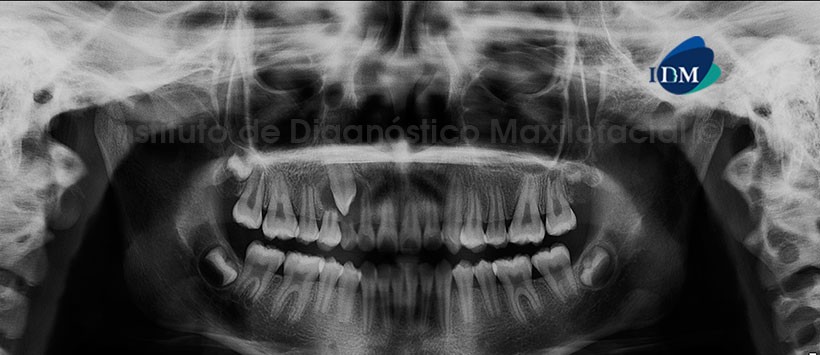

A la evaluación de la radiografía panorámica se aprecia los folículos de las piezas 18, 28, 38 y 48 en evolución intraósea, así como la presencia de la pieza 13 retenida con una imagen radiolucida circunscripta rodeando su porción coronaria de límites definidos y bordes corticalizado;  proyectada sobre las porciones radiculares de las piezas 12, 53 y 14. Además de la presencia de reabsorción radicular externa de las piezas 53 y 14. (Figura 1)